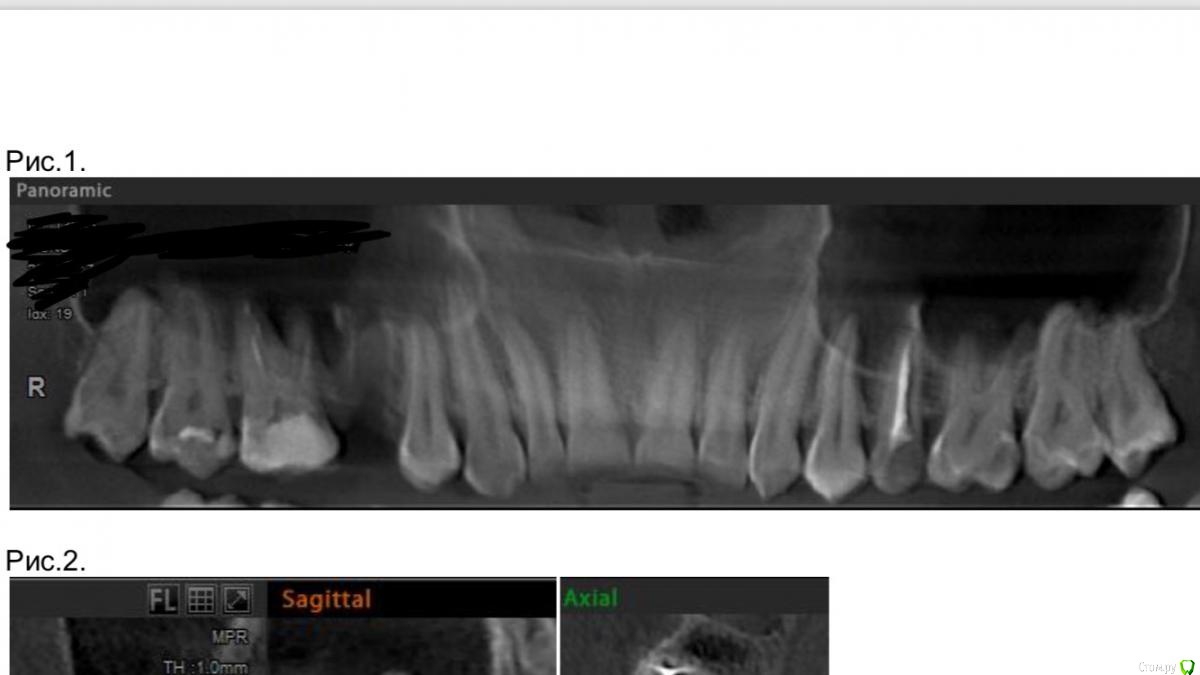

Пушканчик Опубликовано 4 апреля, 2019 Поделиться Опубликовано 4 апреля, 2019 Добрый день! Подскажите, пожалуйста, обязательно ли будет перфорация при удалении зуба с корнями в пазухе? Шестой зуб справа интересует, по КТ апикальные трети выстоят дно пазухи Ссылка на комментарий

___49___ Опубликовано 4 апреля, 2019 Поделиться Опубликовано 4 апреля, 2019 Добрый день! Подскажите, пожалуйста, обязательно ли будет перфорация при удалении зуба с корнями в пазухе? Шестой зуб справа интересует, по КТ апикальные трети выстоят дно пазухиДобрый. Часто при удалении зубов с корнями выстоящими в пазуху , сохраняется целостность слизистой , что не приводит к перфорации( но иногда при активном сморкании , или чихании с закрытом носом - пациент дорывает эту слизистую уже вне стен кабинета стоматолога - будьте аккуратней) . Реже происходит разрыв (перфорация) независимо от действий доктора во время удаления. По Вашему снимку однозначно не ответить . Ссылка на комментарий